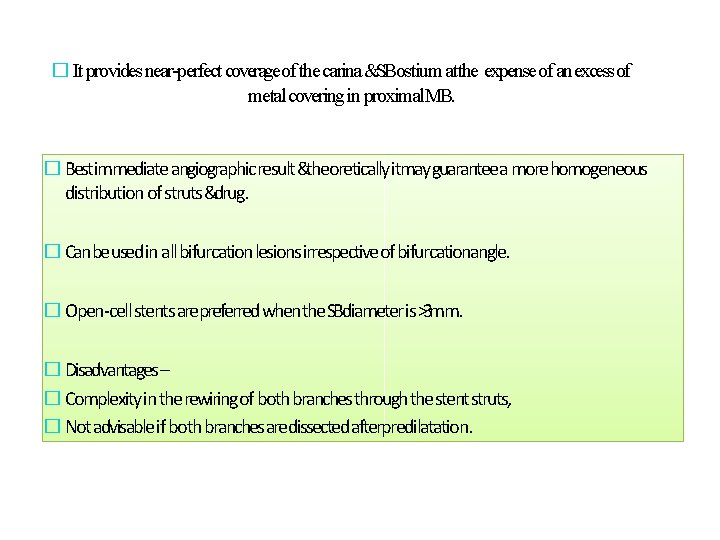

� It provides near-perfect coverageof the carina &SBostium atthe expense of an excessof metal covering in proximal. MB. � Bestimmediate angiographic result &theoretically itmayguarantee a more homogeneous distribution of struts &drug. � Canbeused in all bifurcation lesions irrespective of bifurcationangle. � Open-cell stents arepreferred when the SBdiameter is >3 mm. � Disadvantages – � Complexity in the rewiring of both branches through the stentstruts, � Not advisable if both branches aredissected afterpredilatation.